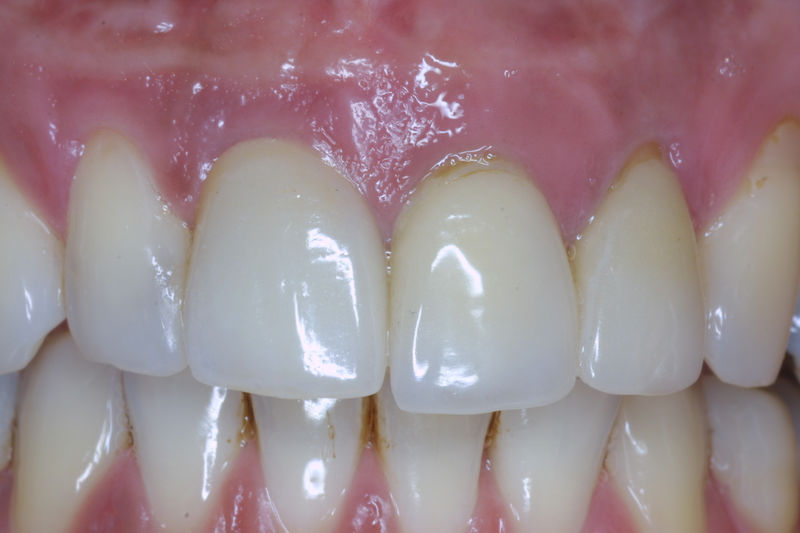

Son restauraciones que cubren toda la cara frontal del diente, generalmente empleadas en el sector anterior y cuya finalidad es primariamente estética.

Restauraciones fabricadas en el laboratorio con materiales estéticos, los cuales cubren de manera total dientes anteriores y posteriores. Se utilizan primariamente para restaurar dientes con caries, fracturas y/o defectos amplios, así como soportes de puentes. Para poder enviar el caso al laboratorio se toman impresiones utilizando materiales de impresión o técnicas modernas digitales.